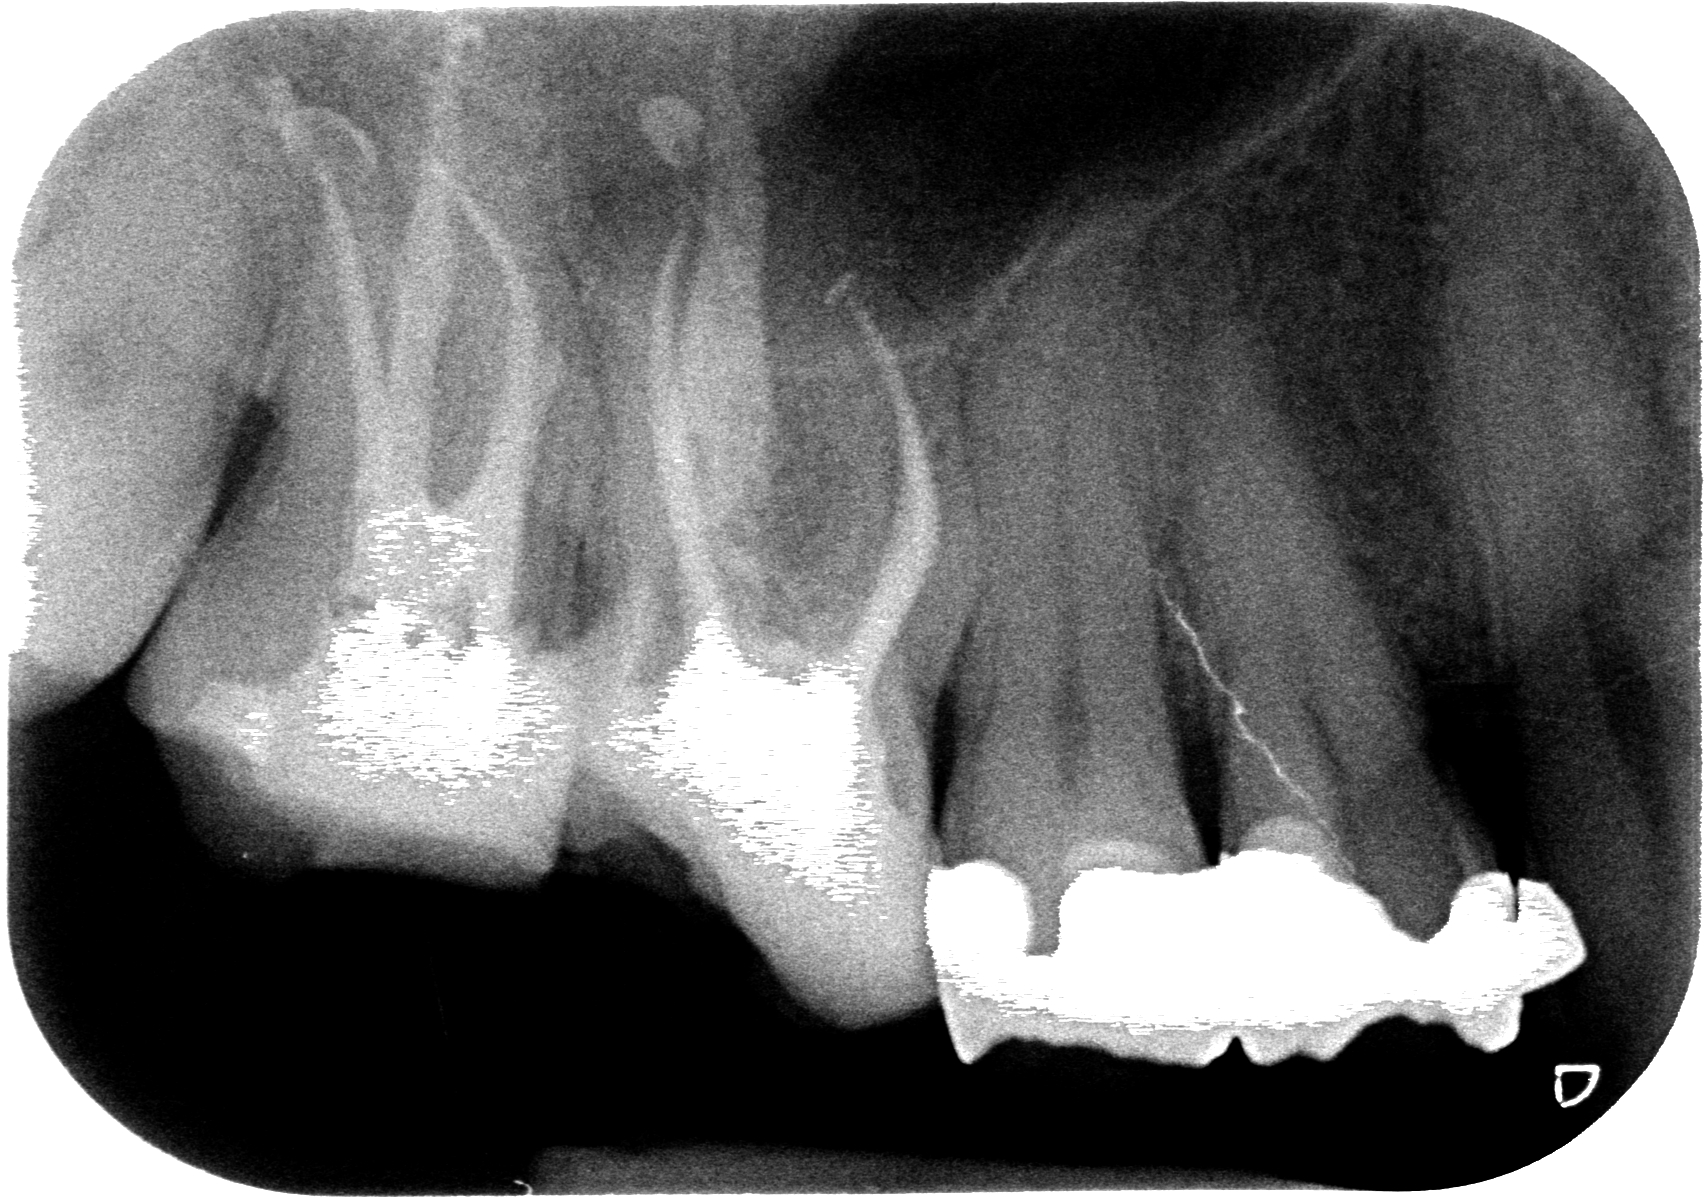

Questo sabato non ha fatto eccezione e mi sono trovato in agenda un ritrattamento di un 1.7 che già dalla radiografia preoperatoria mi ha fatto drizzare le antenne.?

Vedi quel canale mesio-vestibolare? Per esperienza so che quando il dentista che ci ha preceduto è in grado di arrivare in apice su due canali e sul terzo si perde prima della curva di una radice possono essere capitate solo due cose, perchè escludo che sia semplicemente un incapace che non sa fare l’endodonzia:

“Ok, come temevo è molto probabile che siamo finiti fuori strada, facciamo una piccola lastra di verifica per capire dove siamo andati…”

Ed ecco la rx.

A questo punto il paziente non si preoccupa perchè si è verificato esattamente quello che avevi previsto e capisce che la situazione è difficile ma sai cosa stai facendo.